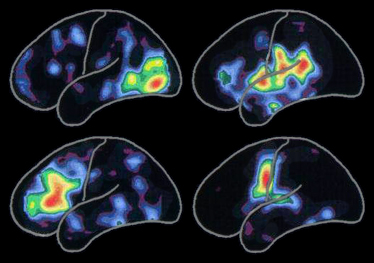

The positron emission tomography (PET) scan on the left shows typical patterns of brain activity associated with:

100 billion nerve cells...100 trillion synapses...dozens of neurotransmitters...This "strength in numbers" provides your brain's raw material. Over time, our experiences create patterns in signal type and strength. These patterns of activity explain how, at the cellular level, our brains code our thoughts, memories, skills and sense of who we are.